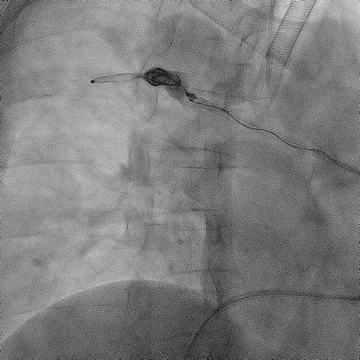

手术过程(三):

交换置入8 F-55 cm长鞘至卵巢静脉近端,经鞘内推送AVP Ⅱ,由于35导丝的强支撑性可以使AVP Ⅱ定位更加精准,选择于近段卵巢静脉释放,鞘内造影见AVP Ⅱ完全释放,VR导管经Stiff导丝置于卵巢静脉远端。

图片